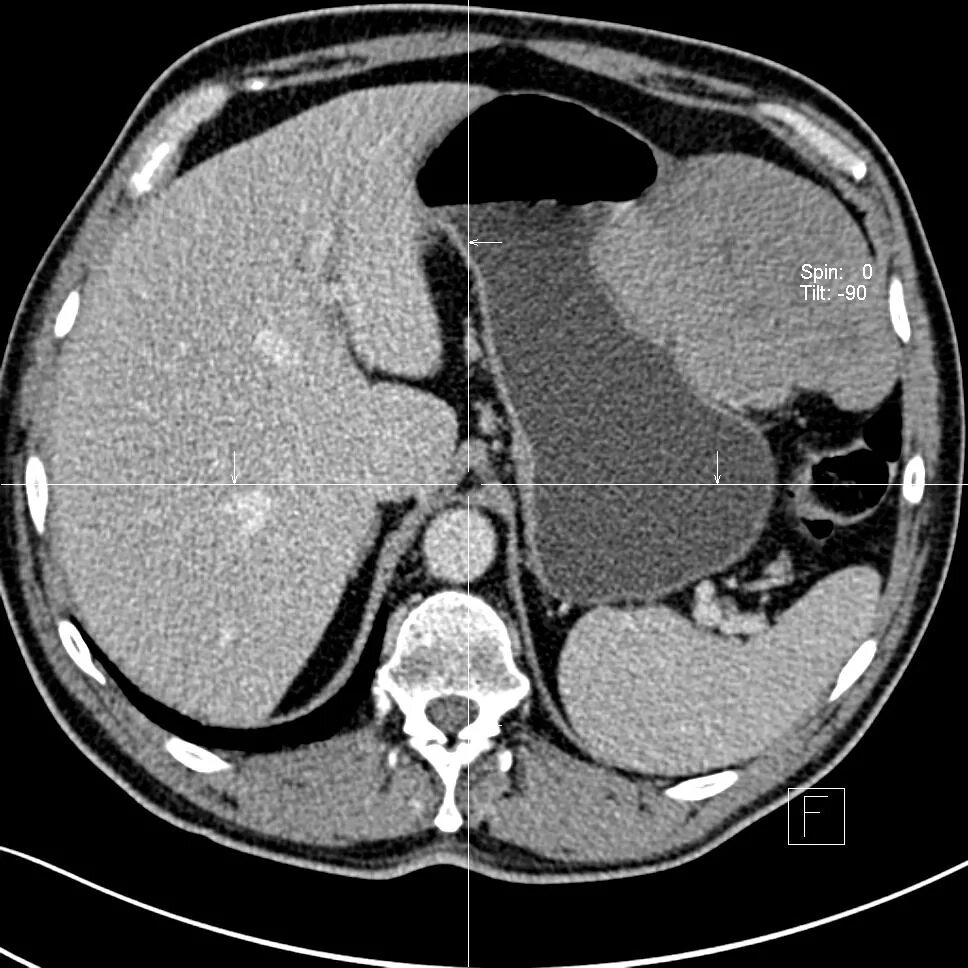

Язва желудка кт